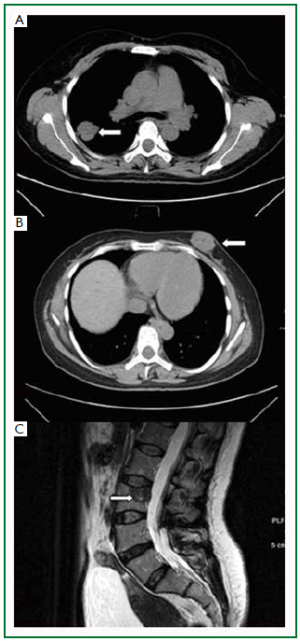

A 40-year-old, non-smoking, business woman presented to the general surgery clinic with a painless, palpable mass in the right breast for 6 days. Physical examination revealed a solid, mobile, and non-tender mass (1 cm × 1 cm) in the upper inner quadrant of the right breast, with irregular border and without skin involvement. Axillary and cervical chain lymph nodes were also not palpable. The CT scan showed a soft tissue mass measured 3.7 cm × 4.2 cm × 4.4 cm located in the inferior lobe of her left lung, with a lobular border (Figure 2A). Patchy shadow, signs of bronchi blockage, and pleural displacement were also noted in the CT images. In addition, a round soft tissue mass with the size of 1cm in diameter was present in the right breast (Figure 2B), and the MRI examination of lower limbs showed a tumor mass in the right femur (Figure 2C).

Figure 2. Preoperative radiology of mass in patient case 2. A: Chest CT image disclosed a soft tissue mass (3.7 cm × 4.2 cm × 4.4 cm) in the inferior lobe of the left lung; B: A 1cm-diamete soft tissue round mass was present in the right breast; C: MRI revealed a metastasis to the right femur. Arrows indicate the tumor lesion.

The right breast lumpectomy and bone biopsy were performed, and the following pathology analysis revealed poorly differentiated adenocarcinoma of the both sites. In addition, epidermal growth factor receptor (EGFR) was detected by immunohistochemistr y staining. The patient underwent two c ycles of Gefitinib treatment but did not demonst rate any s ign of improvement. The patient passed away 8 months after the diagnosis.